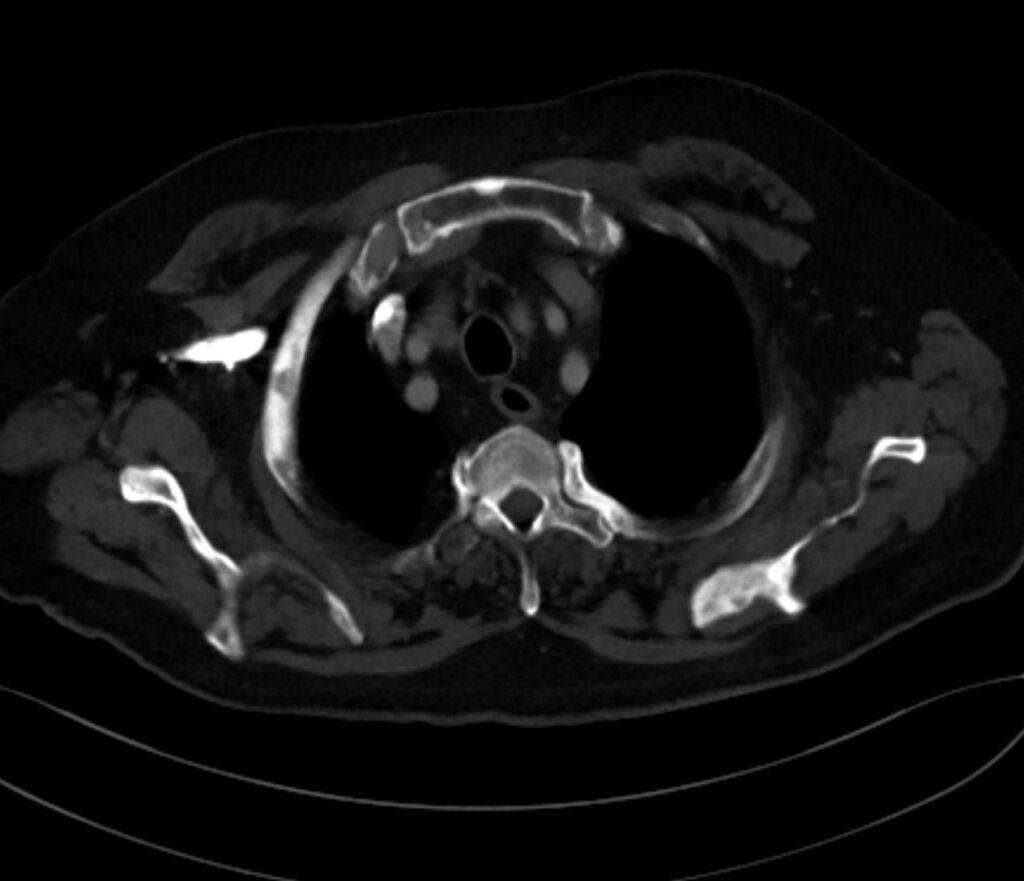

*73-year-old male present with bone pain.

What is the most likely diagnosis?

Sclerotic bone metastases (prostate carcinoma)

CT images revealed sclerotic bone metastases.